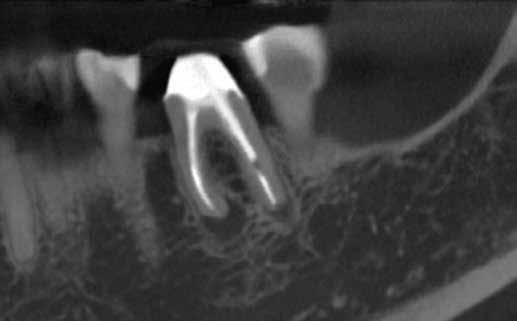

Egy 38 éves nőbeteg a korábban kezelt jobb felső második kisőrlőfogából (1.5) kiinduló mérsékelt fájdalom miatt jelentkezett rendelésünkön. A kórtörténetében jelen panasza szempontjából releváns információ nem szerepelt. A beteg a klinikai vizsgálat során vertikális kopogtatásra enyhe érzékenységet jelzett. A kérdéses fog körül mérhető szondázási mélység és a fogmobilitás fiziológiás volt. Periapicalis röntgenfelvételen egy, a fog gyökércsúcsán túl presszálódott betört gyökérkezelő műszerből származó eszközfragmentumot láttunk (2. a. ábra). A preoperatív CBCT-felvétel a buccalis csontlemez épségét igazolta (2. b-c. ábra). A fog revíziója öt hónappal korábban történt. A már előzőleg gyökérkezelt, gyökértömött, majd revideált 1.5-ös fog esetében a diagnózisunk periodontitis periapicalis symptomatica volt. A periapikális elváltozás kezelése érdekében navigált endodonciai mikrosebészeti beavatkozást végeztünk.

a-m. ábrák: Preoperatív röntgenfelvétel (a) és preoperatív CBCT-felvétel a jobb felső 5-ös (1.5) fogról, sagittalis (b) és axialis (c) nézetek. Az intraorális szkennelés során kapott STL-fájl (d). A 1.5-ös fog navigált endodonciai mikrosebészeti beavatkozásához tervezett sablon (e). A 1.5-ös fog navigált endodonciai mikrosebészeti beavatkozásához nyomtatott sablon (f). Teljes vastagságú mucoperiostealis lebenyt emeltünk (g). A sablont a helyére illesztettük, és a csontablak határait jelöltük (h). A fog gyökerén kívül eső, betört eszköz a 1.5-ös fog periapicalis régiójában (i). Az eltávolított betört eszköz (j). A rezekció, retrográd preparáció és a TotalFill BC RRM Fast Set Putty anyaggal elkészített retrográd gyökértömés utáni röntgenfelvétel (k). A lebenyt varratokkal rögzítettük (l). A kétéves kontroll során készített röntgenfelvétel (m).

A retrográd gyökértömés elkészítése során TotalFill BC RRM Fast Set Putty-t (FKG) használtunk (2. k. ábra). A lebeny széleit 5/0-s Prolene varratokkal egyesítettük (2. l. ábra). A varratok a műtétet követően 72 órával kerültek eltávolításra. A beteg két évvel később kontrollröntgen készítése céljából érkezett rendelőnkbe. A vizsgálat során a fog tünetmentesnek és funkcióképesnek bizonyult (2. m. ábra).